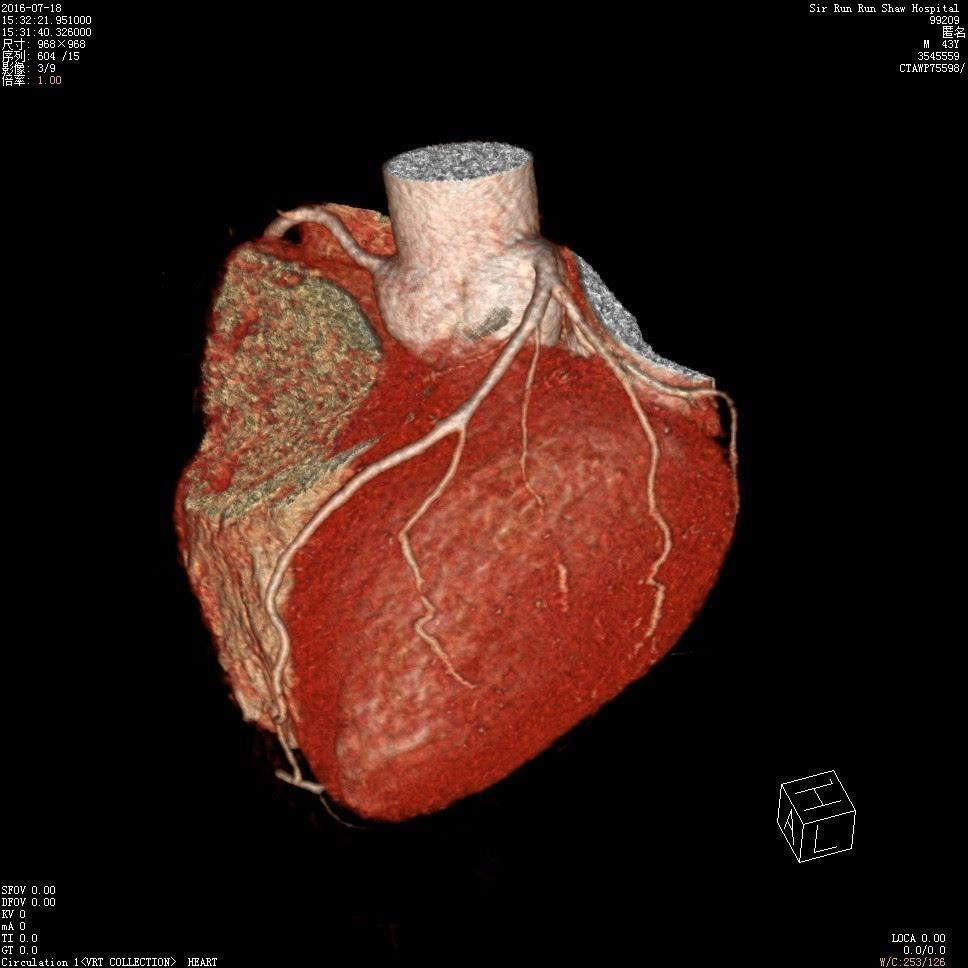

(2)心脏大血管

肺部CT可以看心脏结构有没有问题,心脏大不大,心肌厚不厚,有没有室壁瘤,大血管,肺动脉,主动脉有没有异常,有没有血管瘤,动脉夹层,动脉硬化等等。专门的冠状动脉CT,还可以看供应心脏的冠状动脉有没有粥样硬化,有没有动脉狭窄,狭窄的严重程度,也就是判断有没有冠心病,需不需要放置冠脉支架。冠状动脉的CT可以部分替代冠脉造影检查。

冠脉CT